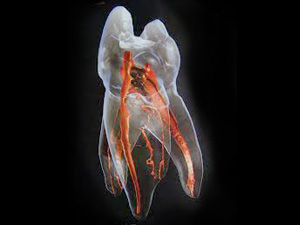

歯には神経が通っており、神経を通して歯は栄養を摂ると同時に痛みや異変なども感じ取ります。

しかし、虫歯が悪化すると細菌は根管にまでおよび、歯の神経まで感染する恐れがあります。

歯が“生きる”ためにもっとも重要な神経。できることなら残しておきたいものですが、残念ながら虫歯が重度まで達した場合、神経を除去しなければならないこともあるのです。

神経を除去し、洗浄・殺菌する……この一連の治療を根管治療といいます。

歯の寿命と神経の関係

歯を木に例えてみましょう。

“生きた”木は土から養分を吸収しているため、なかなか折れることはありません。

しかし“枯れた”木は、どんなに太くて丈夫そうでも、“生きた”木に比べれば折れやすくなります。

歯も同じく、神経を通して栄養(養分)をもらい “生きて”います。

ですが、神経が死んでしまえば栄養を得られず、やがて歯が使えなくなってしまいます。

つまり、神経が死んでしまう=そのままでは歯が“生きて”いられなくなる、ということなのです。